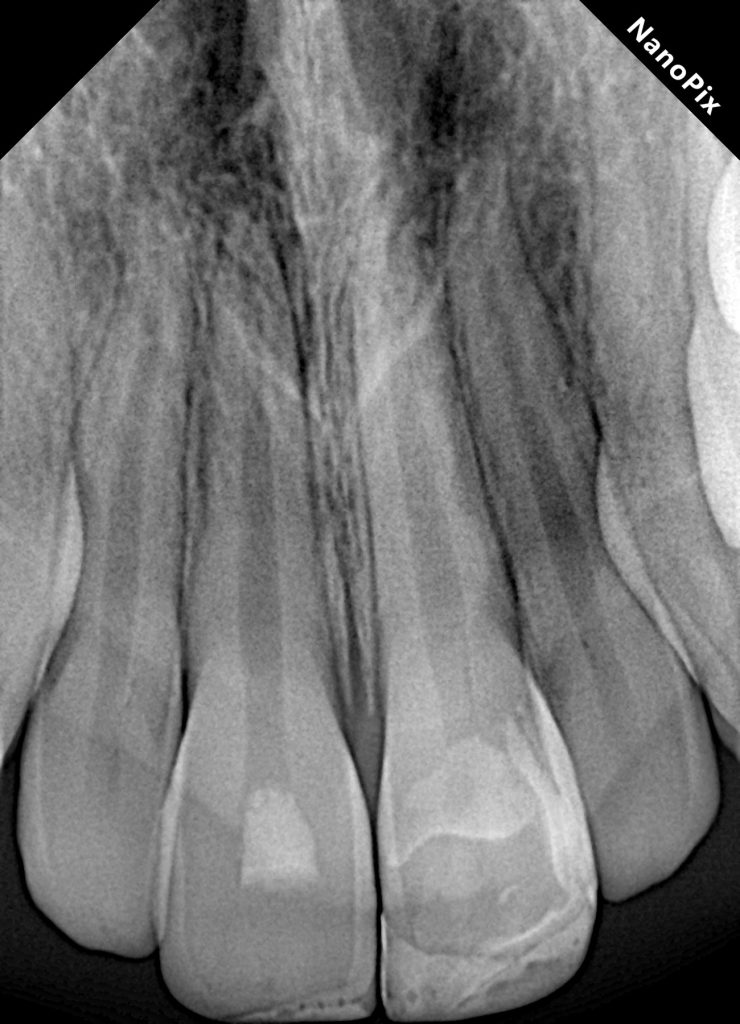

Lower lip soft tissue radiograph

Pre and post operative radiographs